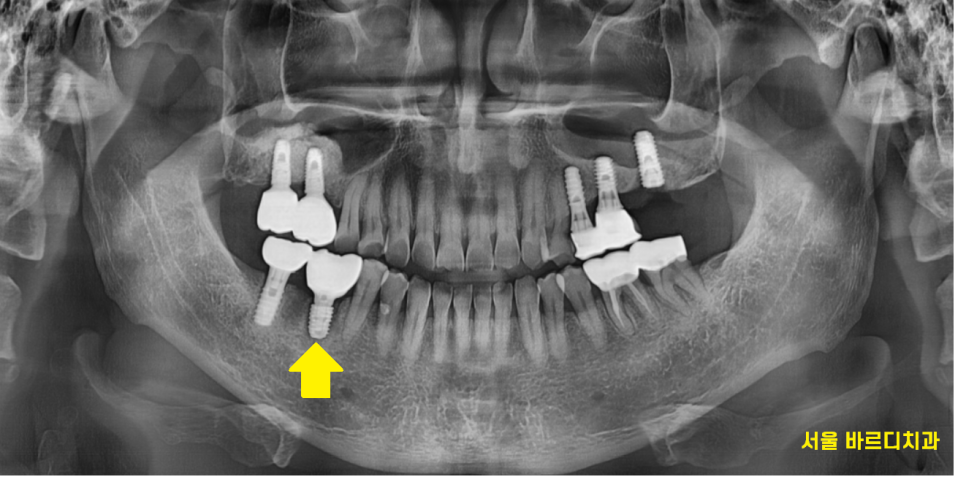

24.08.06

미사역 임플란트 수술 후 2개월 뒤

서울바르디치과를 내원하신 주된 이유인

오른쪽 아래 치료는 끝내드렸습니다.

이제는 왼쪽 위 치아를 수술 후

기다리고 있는 상황입니다.